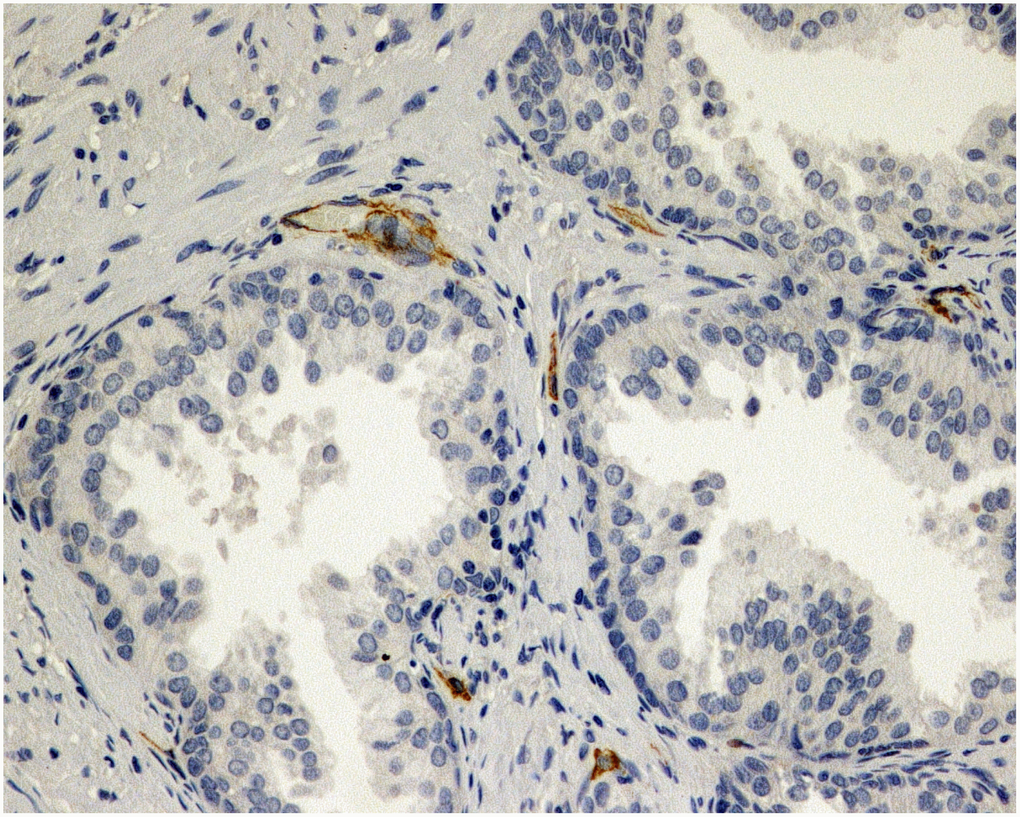

Figure 1. Immunohistochemical evaluation of prostatic tissue of a patient in placebo group - lower expression of MVD (CD34), brown stained spot coloring vessels (x200).

Figure 2. Immunohistochemical evaluation of prostatic tissue of a patient in 5ARI group - higher expression of MVD (CD34), brown stained spot coloring vessels (x200).

The present trial also found a difference between the placebo group and patients treated with dutasteride in terms of microvascular density and vascular endothelial growth factor during pathological evaluation following laser prostate enucleation. MVD and VEGF index values were significantly better in those given dutasteride therapy and the pattern was present in patients both with smaller and larger prostate volumes. Another study assessed prostatic tissue of the bladder neck and apex for MVD and reported that pretreatment with dutasteride reduced microvascular density and may lead to decreased risk of perioperative prostatic urethral bleeding [21].

Tissue specimens stained with hematoxylin and eosin were fixed in 10% buffered formalin and embedded in paraffin. Sections were cut and slides were dewaxed in xylene and rehydrated through a graded series of ethanols. Heat-induced epitope retrieval was carried out by immersing the slides in citrate buffer (pH 6) and microwaving at 600 W for 20 minutes before rinsing with phosphate-buffered saline (PBS). Endogenous peroxidase activity was quenched by incubating the sections in 1% hydrogen peroxide. Nonspecific binding sites were then blocked by preincubating with 20% normal serum and 1% bovine serum albumin (BSA) in PBS/0.3% Triton X-100 (Union Carbide, Dow Corporation, Midland, MI) for 20 minutes at room temperature. Sections were incubated with polyclonal rabbit anti-VEGF antibody at a concentration of 1:50, as well as monoclonal murine anti-CD34 at a concentration of 1:20. After washing with 0.25% BSA and 0.05% polysorbate 20 in PBS, sections were incubated with biotinylated secondary pan-specific antibody at 1:500 for 1 hour at room temperature. Sections were again washed in PBS with 0.05% polysorbate 20, then incubated with horse radish peroxidase and conjugated streptavidin-biotin complex for 45 minutes. All sections were again washed in PBS with 0.05% polysorbate 20. Immunoreactivity was then visualized by adding hydrogen peroxide as an enzyme substrate, in the presence of 0.05% 3,3′-diaminobenzidine. Nuclei were then lightly counterstained with Harris’s hematoxylin. The area of most intense neovascularization was selected by scanning on low magnification (10-100×), avoiding areas with lymphocytic infiltration or fibrosis. Any brown-staining endothelial cell (CD34-positive) containing a visible nucleus and clearly separate from adjacent microvessels, epithelial cells, and other connective tissue elements, was considered a single, countable microvessel, without requirement for a lumen or the presence of erythrocytes. The microvessels were counted in a 0.74-mm2 area. VEGF immunoreactivity was scored for the percentage of stained epithelial glandular and endothelial cells, as 0, 1+, 2+, or 3+, according to staining intensity. A hypertrophic area with any degree of staining was scored as VEGF-positive. Hyperplastic areas that were VEGF-positive and VEGF-negative were assigned the score of the area with strongest staining Figures 1 and 2.